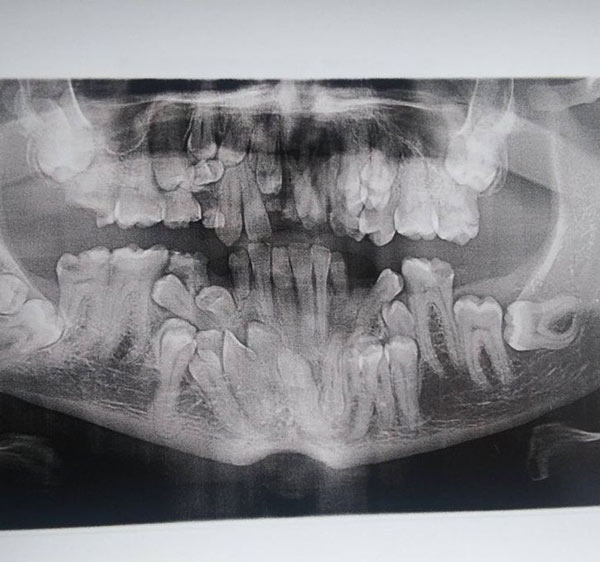

Tôi mắc chứng loạn dưỡng chất trong sọ, một hội chứng rối loạn hiếm gặp. Đây là bức ảnh chụp X-quang nha khoa đầu tiên của tôi, hóa ra tôi có rất nhiều răng thừa.